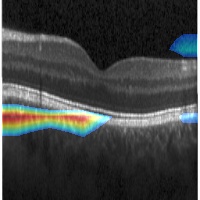

Figure 3: ROI obtained for training with different types of local annotation.

Next, we present the results of experimenting with different types of localization of suspect regions during training. Fig.3 shows the derived ROIs for 2 sample images. It can be seen that ROI is less and less localised as the precision with which local annotations used in training data is compromised, which is to be expected. Quantitatively, accuracy of classification remains above 90 % for all types of local annotations used (see Table 3). However, there is a fall in accuracy of correct ROI predictions for a bounding box type of annotation and a steep degradation when the whole image or random patches are used as annotations. More results are shown in Fig.4 for 1:3 training regime. A comparison of the classification accuracy of the proposed method with 2 state of the art (SOTA) methods are given in Table 4. Our method is seen to be almost on par with [12] for 4 metrics, when tested on the same large dataset [7].